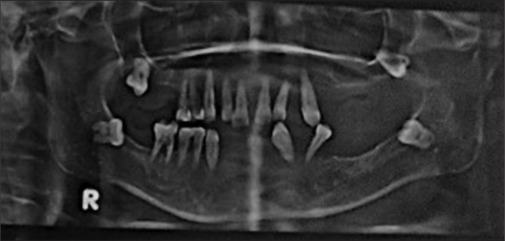

药物性牙龈肿大通常是由于患者对处方药的副作用缺乏认识而发生的。本病例报告详细介绍了一位50岁女性的罕见的大量药物引起的牙龈过度生长,通过多学科方法,包括手术干预和假肢康复,成功地进行了治疗。手术治疗包括多次摘除和切除多余组织。手术后两足弓完全愈合,患者接受了假肢康复治疗,无复发迹象。此类病例的有效管理依赖于患者咨询和适当的药物替代。提高对某些药物的副作用以及全身和口腔健康之间的联系的认识对于预防这类牙龈肿大的病例至关重要。

Drug-induced gingival enlargement often occurs due to patient's lack of awareness about the side effects of prescribed medications. This case report details an unusual instance of massive drug-induced gingival overgrowth in a 50-year-old female, successfully managed through a multidisciplinary approach, including surgical intervention and prosthetic rehabilitation. The surgical treatment involved multiple extractions and the excision of excessive tissue. Both arches healed completely after surgery, and the patient underwent prosthetic rehabilitation, with no signs of recurrence. Effective management of such cases relies on patient counseling and appropriate drug substitution. Increasing awareness about the side effects of certain medications and the connection between systemic and oral health is crucial to prevent such cases of gingival enlargement.